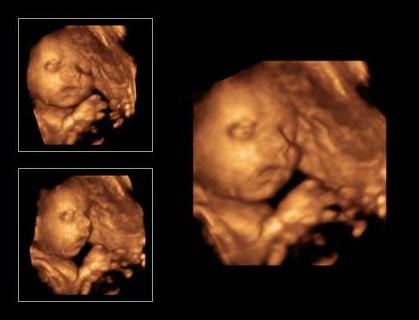

A Milán amúgy végig magyarázott :shock: :D folyamatosan járt a szája ...láttuk ahogy hatalmasra nyitja a száját még az orrát is felhúzta és majszolja a köldök zsinórt,ami pont az arca előtt van nagy kupacba...ezért nem látszott teljesen a pofija.

Teszek róla képet de nem sok látszik belőle max az orra h felhúzta ...meg ha jól megnézitek látszik,hogy mekkora a szája és benne van a zsinór :D Kép

Ezen is a zsinór a sláger itt már puszilgatta :D Kép